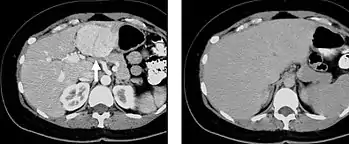

Computed tomography

When evaluating hepatic masses by abdominal computed tomography (CT), it can be advantageous to have both late arterial and portal venous phase images since some tumors enhance briskly during the arterial phase (hepatocellular carcinoma, hepatic adenoma, follicular nodular hyperplasia (FNH), and hypervascular metastasis), but maybe occult or difficult to characterize on portal venous phase imaging alone. However, it should be stressed that the addition of late arterial phase images is only indicated if one of these tumors is suspected, or if there is a need for further characterization of a hepatic mass, since the large majority of patients will not benefit from the addition of this phase. In addition, if there is a need to definitively characterize a hepatic mass, MRI is generally more sensitive and specific, with no associated radiation dose.